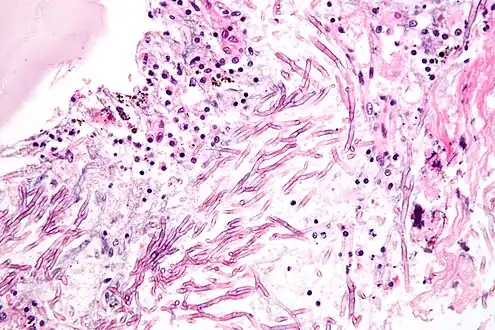

| H&E stain showing a fungal pneumonia (pulmonary aspergillosis) | |

Fungal pneumonia is an infection of the lungs by fungi. It can be caused by either endemic or opportunistic fungi or a combination of both. Case mortality in fungal pneumonias can be as high as 90% in immunocompromised patients,[1][2] though immunocompetent patients generally respond well to anti-fungal therapy.

- Aspergillosis, resulting in invasive pulmonary aspergillosis